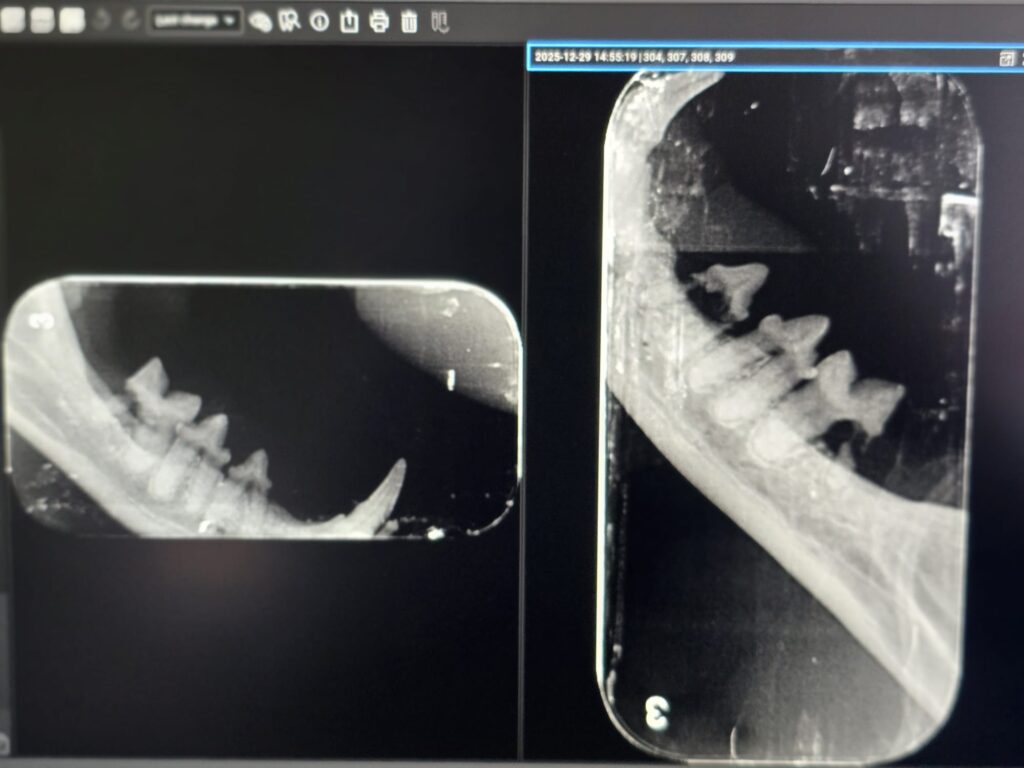

Importanța radiologiei dentare în diagnosticul resorbției dentare

Resorbția dentară este adesea invizibilă la suprafața dintelui. Din acest motiv, radiografiile dentare sunt indispensabile.

În cadrul clinicii Certovet, utilizăm:

- radiologie dentară dedicată

- evaluarea completă a rădăcinilor dentare

- stabilirea exactă a stadiului leziunilor

- planificarea corectă a intervenției chirurgicale

Fără radiografie, multe leziuni rămân nediagnosticate sau subevaluate.